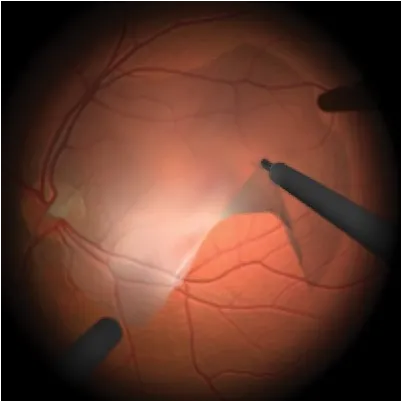

CIRUGÍA DE RETINA

CIRUGÍA DE RETINA

Cirugía para desprendimiento de retina, hemorragia vítrea, retinopatía diabética, agujero macular con la mejor tecnología.